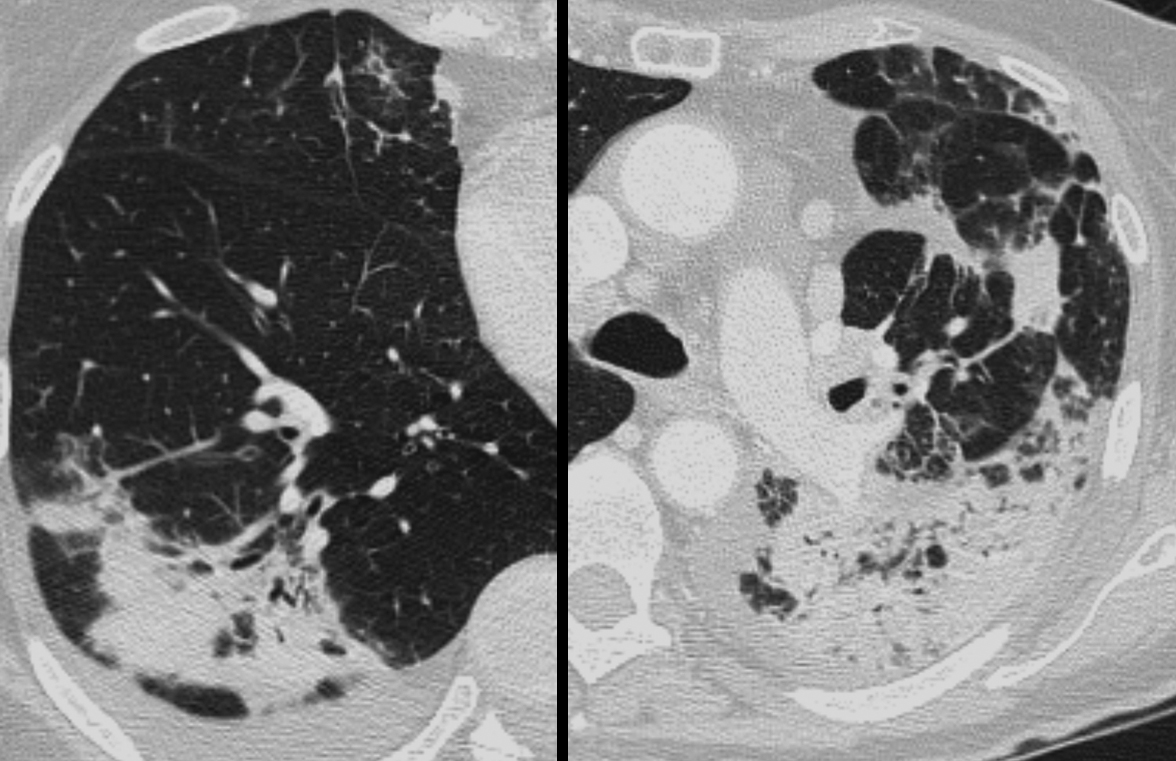

Eos pneum CT